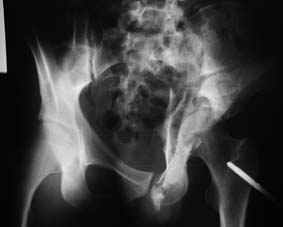

Все-таки надо бы начать не с КТ, а с обзорного снимка таза и косых проекций впадины.

Это обзорные и косые снимки

С уважением,

Leonid

Привет, Леонид. Оскольчатый высокий двухколонный перелом в такие сроки трогать не надо, т.к. это про такие переломы сказано: "кто с ножом на Ж. пойдет тот в ней и останется...".

Может быть неплохой результат при консервативном лечении и ранних движениях.

Если заболит после начала нагрузки в 4-6 месяцев - эндопротез.